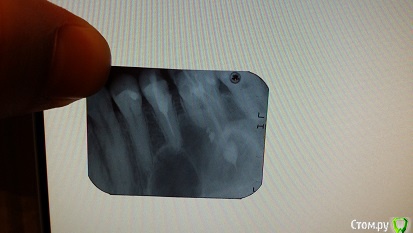

natali777 Опубликовано 6 января, 2016 Автор Поделиться Опубликовано 6 января, 2016 прицельный снимок за месяц до удаления 1 Ссылка на комментарий